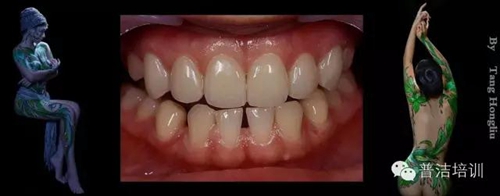

部分病例:

改變了什么?